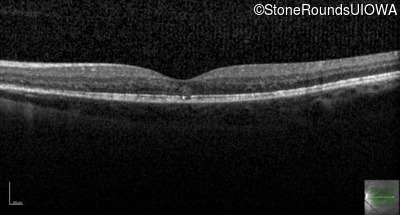

Optical Coherence Tomography - Left - 20/50

Exemplar / OCT Stack